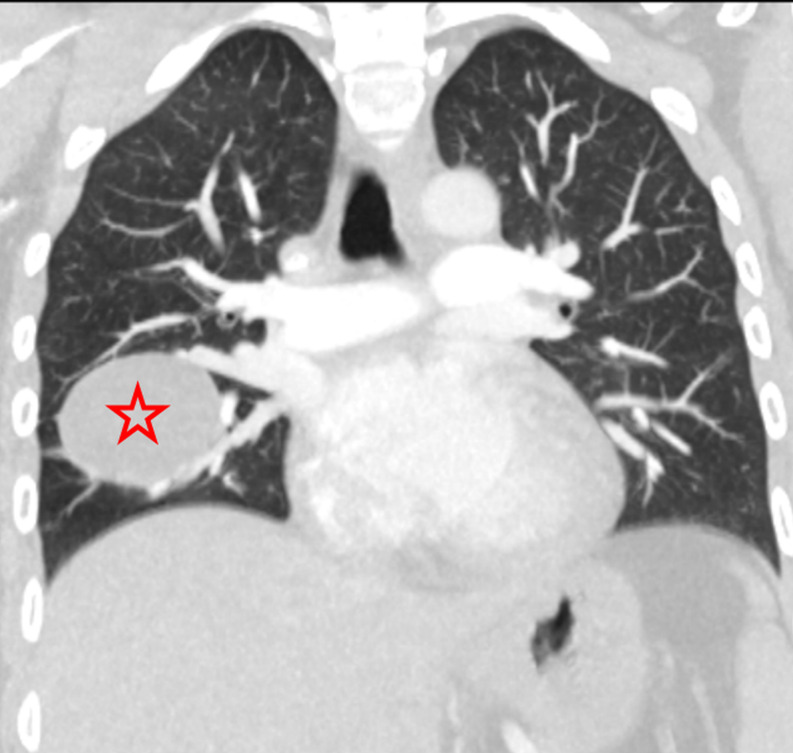

Abstract Image